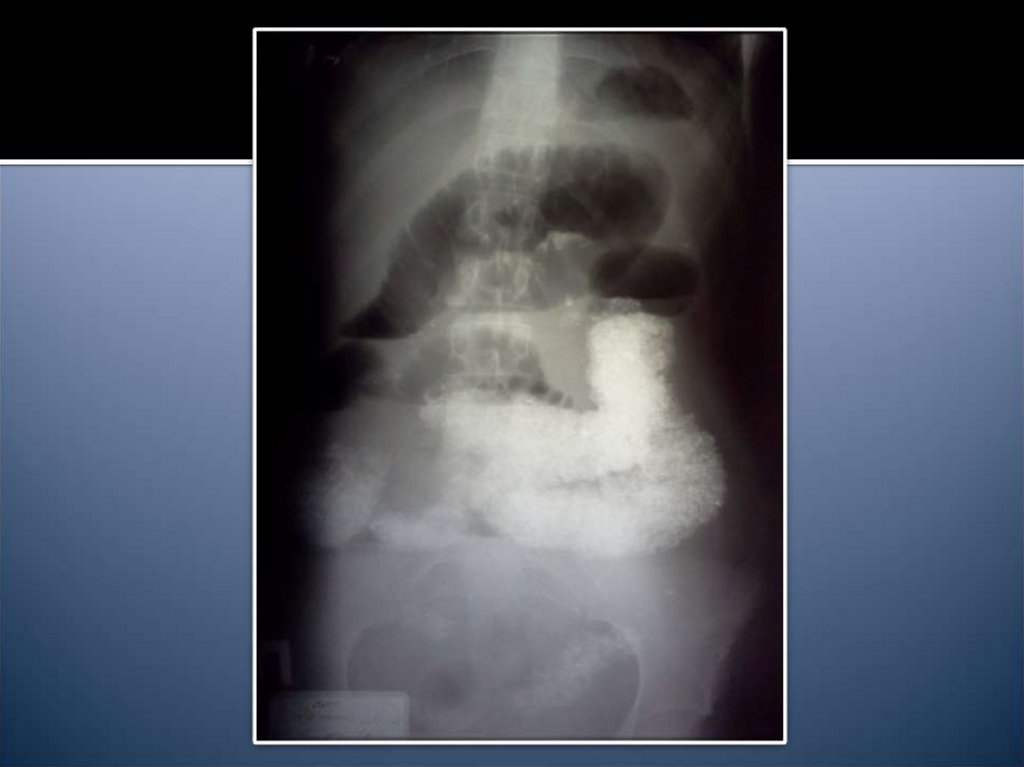

14. Рентгенологические признаки

Чаши Клойбера

Симптом Кивуля (аркады)

Проба Шварца

Пневматоз петель кишечника